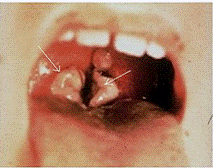

Рисунок 4. Лакунарная ангина: слизистая глотки воспалена, на миндалинах гнойный налет

При осмотре глотки можно увидеть покрасневшие (гиперемированные), увеличенные миндалины, с точечными желтоватыми образованиями (2-3 мм) при фолликулярной и фибринозно-гнойными налетами неправильной формы при лакунарной ангине.

Рисунок 5. Ангина в стадии выздоровления, после отхождения гнойных масс можно видеть расширенные лакуны

В тяжелых случаях ангины в миндалинах могут возникать участки омертвения (некроза) темно-серого цвета, которые затем отторгаются, а на их месте образуются дефекты ткани размером до 1 см, часто неправильной формы с неровным дном.